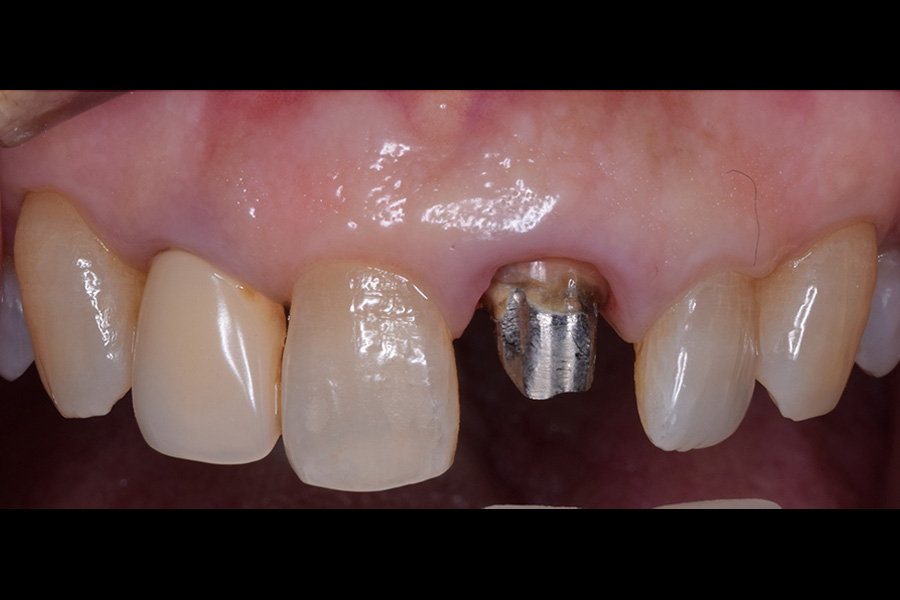

治療前

| 主訴 | 検診してほしい 銀歯の下が虫歯になっていたため治療 |

| 治療内容 | 虫歯治療、セラミックブリッジ治療 |